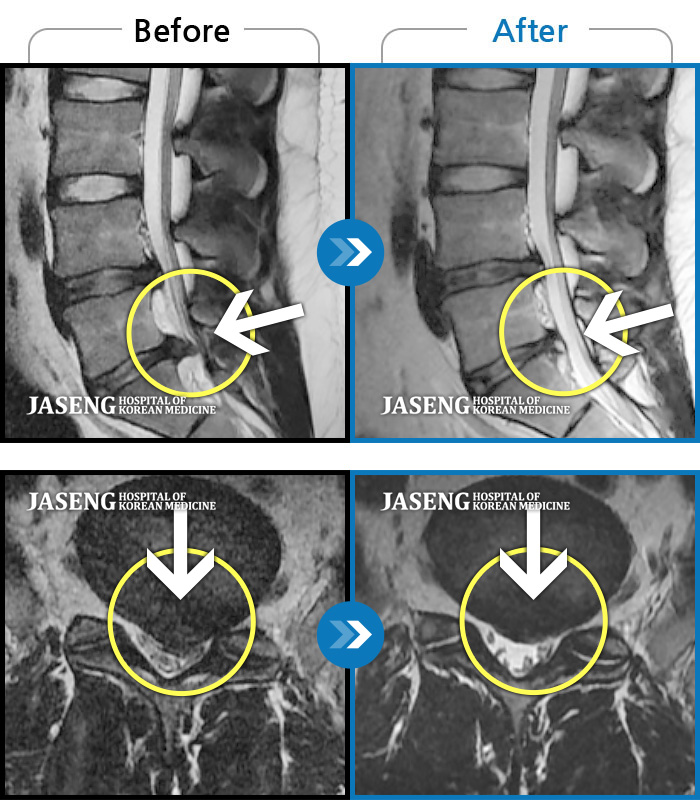

24년 3월 디스크파열 진단받고 극심한 통증으로 입원하여 김재영원장님께 치료받은 후 증상이 매우 호전되어 퇴원한 경험이 있습니다. 원장님께서 퇴원무렵 컨디션 관리를 엄청 당부하셨지만 근무하는 과정에서 발생하는 어쩔수 없는 과로와 극심한 스트레스는 서서이 좋아지던 저의 디스크 통증을 급기야 재발하게 만들었습니다. 7월말 다시 시작된 왼쪽 종아리와 발가락으로 퍼지는 심한 통증과 몸살로 더이상 근무를 계속할수 없어서 급하게 원장님을 뵙고 입원 치료하게 되었습니다. 김재영 원장님께 진료받고 극심했던 방사통이 진통제 없이 생활하기 까지 호전된 경험이 있고 원장님께서도 저의 상황을 어느정도 아시고 계셔서 이번에는 처음 디스크 터졌을때처럼 엄청 겁먹지 않고 원장님께 사소한 증상 하나하나 말씀드리면서 차분하게 치료받을 수 있었습니다. 제가 직장다니면서 힘든 마음으로 다시 입원하게 된 상황을 이해해 주시고 치료가 빠르게 될수 있도록 매일 소소한 증상 하나하나 신경쓰셔서 치료해주시고자 애써 주셔서 진심으로 감사했습니다. 심한 몸살이 디스크 통증과 함께 와서 소화도 안되고 기운도 없이 입원 첫주 무척 힘든 시간을 보냈습니다. 원장님께서는 소화가 잘 되게 침치료도 병행해 주시고, 소화제 종류도 다양하게 바꿔가며 저의 컨디션이 되돌아 올수 있게 처방을 해 주셨습니다. 무수히 많은 환자를 진료하시는 바쁘신 진료시간 중에서도 저의 증상을 매일 편하게 말씀 드릴수 있게 대해 주셔서 소소한 증상까지 말씀 드려 본의 아니게 원장님을 피곤하게 해드렸습니다. 입원 9일차 정도되니 그렇게 아팠던 종아리 통증은 거의 사라지고 소화기능도 조금씩 회복되고 있습니다. 통원치료때도, 입원치료때도 늘 한결같이 저의 증상을 귀담아 들어주시고 치료가 빠르게 될수 있도록 애써 주셔서 고맙습니다. 침 치료시에 어쩔수 없이 듣게 되는 다른 환자분들과 원장님과의 대화속에서도 치료받으시는 어버님 아버님들께서 원장님께 아픈 곳을 편히 말씀하시는것이 느껴졌습니다. 원장님께서도 일일이 다 성의껏 어르신들 말씀 귀담아 들어주시고 치료해 주시는것을 보니 원장님께서는 참으로 인품마저 다정하신 분 같았습니다. 거기에 아픈 통증도 꼭꼭 잡아주시니 원장님께 진료받는 많은 환자들이 원장님의 마음에 심적으로 안정을 받으시고 원장님의 전문적인 의료 도움을 크게 받는것 같습니다. 원장님께서 환자를 대해 주시는 따뜻함, 실력있는 의술 덕분에 제가 입원하는 기간 마음 편하게 치료 받을수 있었습니다. 통증이 자주 재발하면 완치되기가 힘드니 조심해야 된다는 원장님 조언 잘 새겨듣고 올 하반기에는 다시 입원하지 않도록 노력해 보겠습니다. ^^ 원장님께서도 남은 여름 건강 잘 챙기세요~~~ 고맙습니다. 김재영 원장님 ^^

저는 허리디스크 파열로 3월 1일부터 입원하여 3주째 해운대 자생 김재영 원장님께 입원진료를 받고 있습니다.

이번주에 퇴원할 예정이라 그동안 원장님께 진료 받고 조금씩 나이지고 있는 부분에 대해 진심으로 감사한 마음을 전하고 싶습니다.

허리 디스크 파열이라는 사실을 모르고 단순하게 허리디스크가 조금 튀어나왔을거라고 생각하고 이전 교통사고로 생긴 두통 치료를 김재영 원장님께 진료받고 나은 기억이 있어 혹시나 하여 원장님과 상담을 했습니다.

김재영 원장님께서 혹시 모르니 그래도 MRI를 찍어보고 정확히 원인을 알고 치료를 하자고 권유하셔서 MRI를 찍게 되었습니다. 결과는 디스크 파열로 심각한 상황이었습니다.

저는 수술이 당장 시급한, risk가 상당히 있는 MRI 결과였지만 갑작스러운 결과에 수술을 바로 하기엔 너무 겁이 나서 일단 입원하여 원장님 치료를 받아보기로 마음먹고 바로 입원했습니다.

지옥같은 1주일이 지나고 아주 조금씩 방사통이 약해지기 시작했고 지금 입원 3주차에 접어들어서는 그렇게 심했던 방사통은 낮에 근무가 가능할 정도로 호전되었습니다.